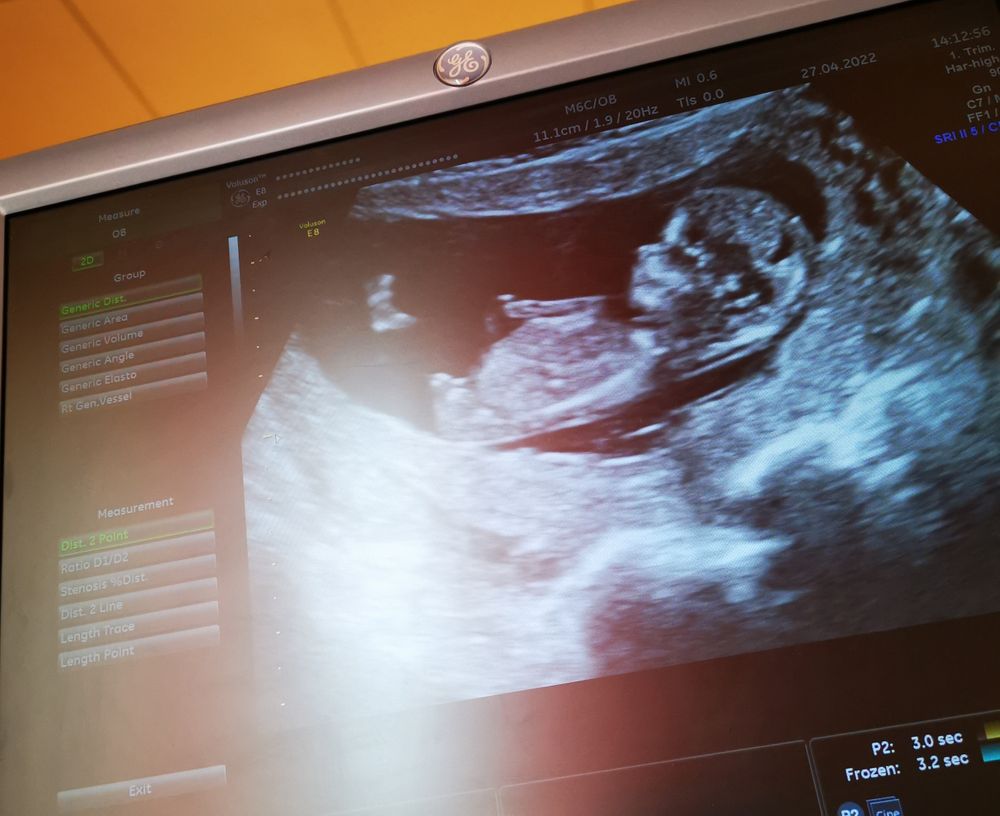

Добрый день. Согласна с комментариями, которые были ранее. Высоко вероятно по половому бугорку, что у Вас внутри мальчишка:) К сожалению, так как все дело в углу между бугорком и спинкой малыша, есть небольшая вероятность ошибки. Однако у Вас очень похоже(: Удачи!

Мальчик, писюшка мальчика🙂

Мальчик мне кажется)

Я тоже за мальчика, бугорок вверх смотрит)

Кажется, что половой бугорок не опущен - мальчик)

Мне кажется мальчик ))